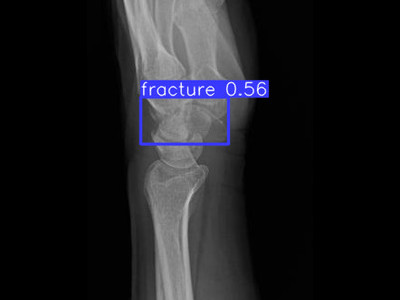

Detecção de fratura do rádio distal em Raio X

Fratura do rádio distal